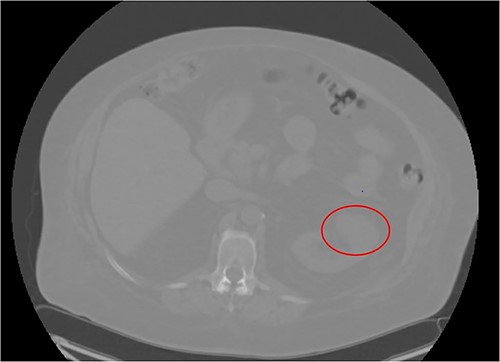

A 66-year-old morbidly obese female with relevant past medical history of type 2 diabetes mellitus, hypertension, and end stage renal disease on peritoneal dialysis (PD) was found to have an incidental enhancing right renal mass concerning for neoplasm on computerized tomography (CT) urogram workup for bacterial peritonitis secondary to streptococcus agalactiae bacteremia (Figs 1 and 2). After appropriate antibiotic treatment and discharge, the patient followed up in clinic where review of the incidental exophytic 16 mm renal mass confirmed suspicions for renal cell carcinoma. The patient still produced urine and was on the transplant list, but wished to proceed with RAPN of the suspicious lesion. A decision was made to use the patient’s PD catheter given her preoperative score of >3 on the Hostile Abdomen Index [5]. In addition to history of bacterial peritonitis, the patient had a notable past surgical history of open cholecystectomy, umbilical hernia repair, and laparoscopic peritoneal dialysis catheter placement in the past 3 months. She was also awaiting a transplant donor, and wished to remain on the list. In the operative theater, her double-cuffed Tenckhoff PD catheter was capped and prepped into the sterile field. Insufflation tubing was connected to the PD catheter and pneumoperitoneum was achieved with normal opening pressure. Laparoscopic trocars were sequentially placed and RAPN was completed without complication. The patient’s post-operative course was unremarkable. Upon physical examination at her 1 month follow-up, her incision sites remained clean, dry, and intact with no complaints of pain. She denied dysuria and gross hematuria. She was cleared to restart peritoneal dialysis at that time. Subsequent pathologic examination of the renal mass confirmed Type 2 Renal Cell Carcinoma with pathologic stage classification T1a, N0 and no signs of regional lymph node metastasis. The patient was instructed to follow-up in 6 months but was ultimately lost to follow-up on our urologic service.

CT Urogram demonstrating a 1.6 cm enhancing right renal mass suspicious for renal cell carcinoma.

CT Urogram demonstrating right renal mass suspicious for neoplasm.